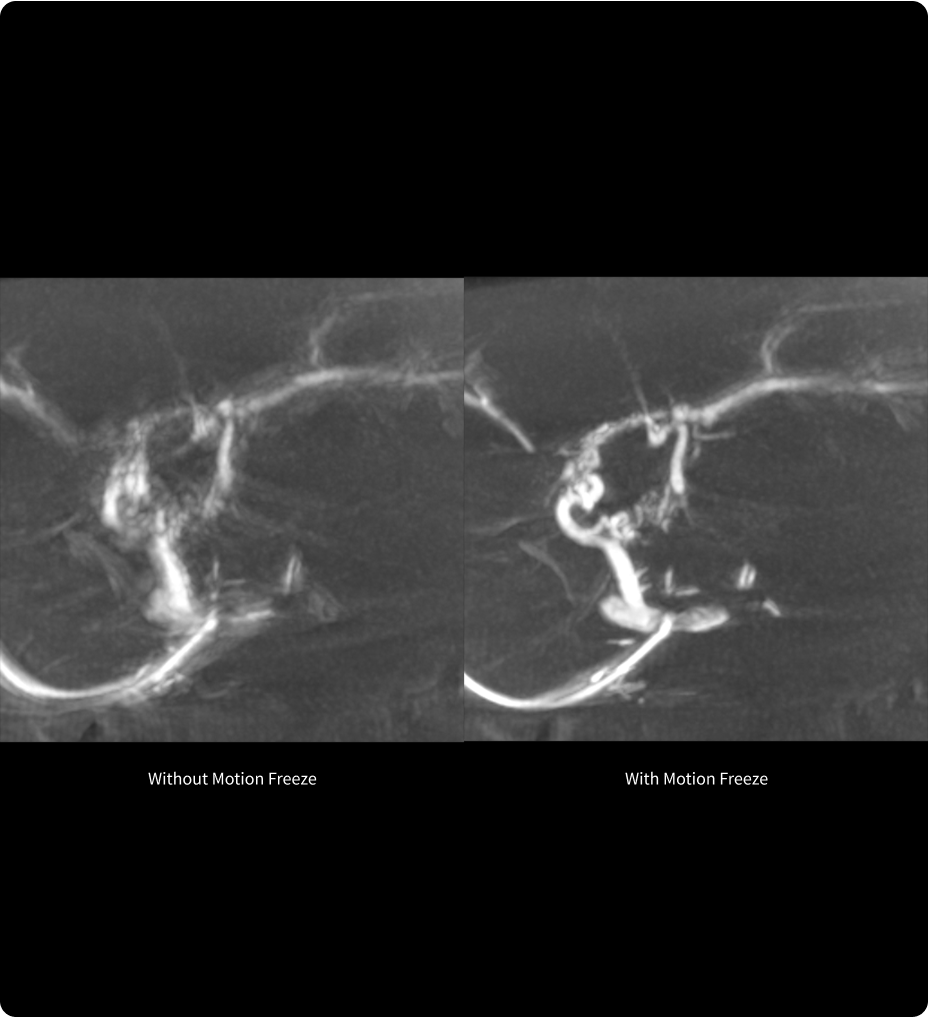

Motion Freeze6,7

Compensez les artefacts respiratoires, réduisez la dose de rayonnement.

Motion Freeze est une solution innovante qui réduit considérablement les artefacts de mouvement causés par les mouvements respiratoires involontaires, améliorant ainsi la clarté et la précision des images CBCT.8. Elle permet de corriger les artefacts de mouvement en une seule acquisition, réduisant ainsi la nécessité de répéter les acquisitions et minimisant ainsi l’exposition au rayonnement et l’utilisation de produits de contraste.9.

En offrant une option rapide de post-reconstruction, Motion Freeze simplifie le flux de travail en permettant la récupération et l’utilisation des acquisitions CBCT initiales qui, autrement, auraient été ignorées.10.